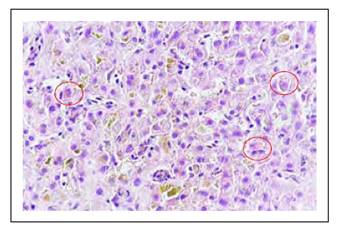

Los hallazgos histológicos en la biopsia hepática se muestran en las Figuras 1 a 6.

Figura 2 Los espacios porta mostraron leve infiltrado inflamatorio mixto a linfocitos, polimorfonucleares, que no rebasan la placa limitante. Uno de los 14 espacios porta de la biopsia muestra infiltrado inflamatorio mixto, leve, que no rebasa la placa limitante, en el acino se observan linfocitos y polinucleares. Se observa además linfocitos agrediendo el endotelio de la vénula de la microvasculatura portal.